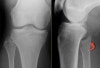

X-ray : 비골 근위부 골절(Proximal fibula fracture)

무릎의 AP & lateral view 외에 oblique view를 시행합니다.

무릎의 불안정성이 발견되거나 의심되면 MRI를 시행합니다.